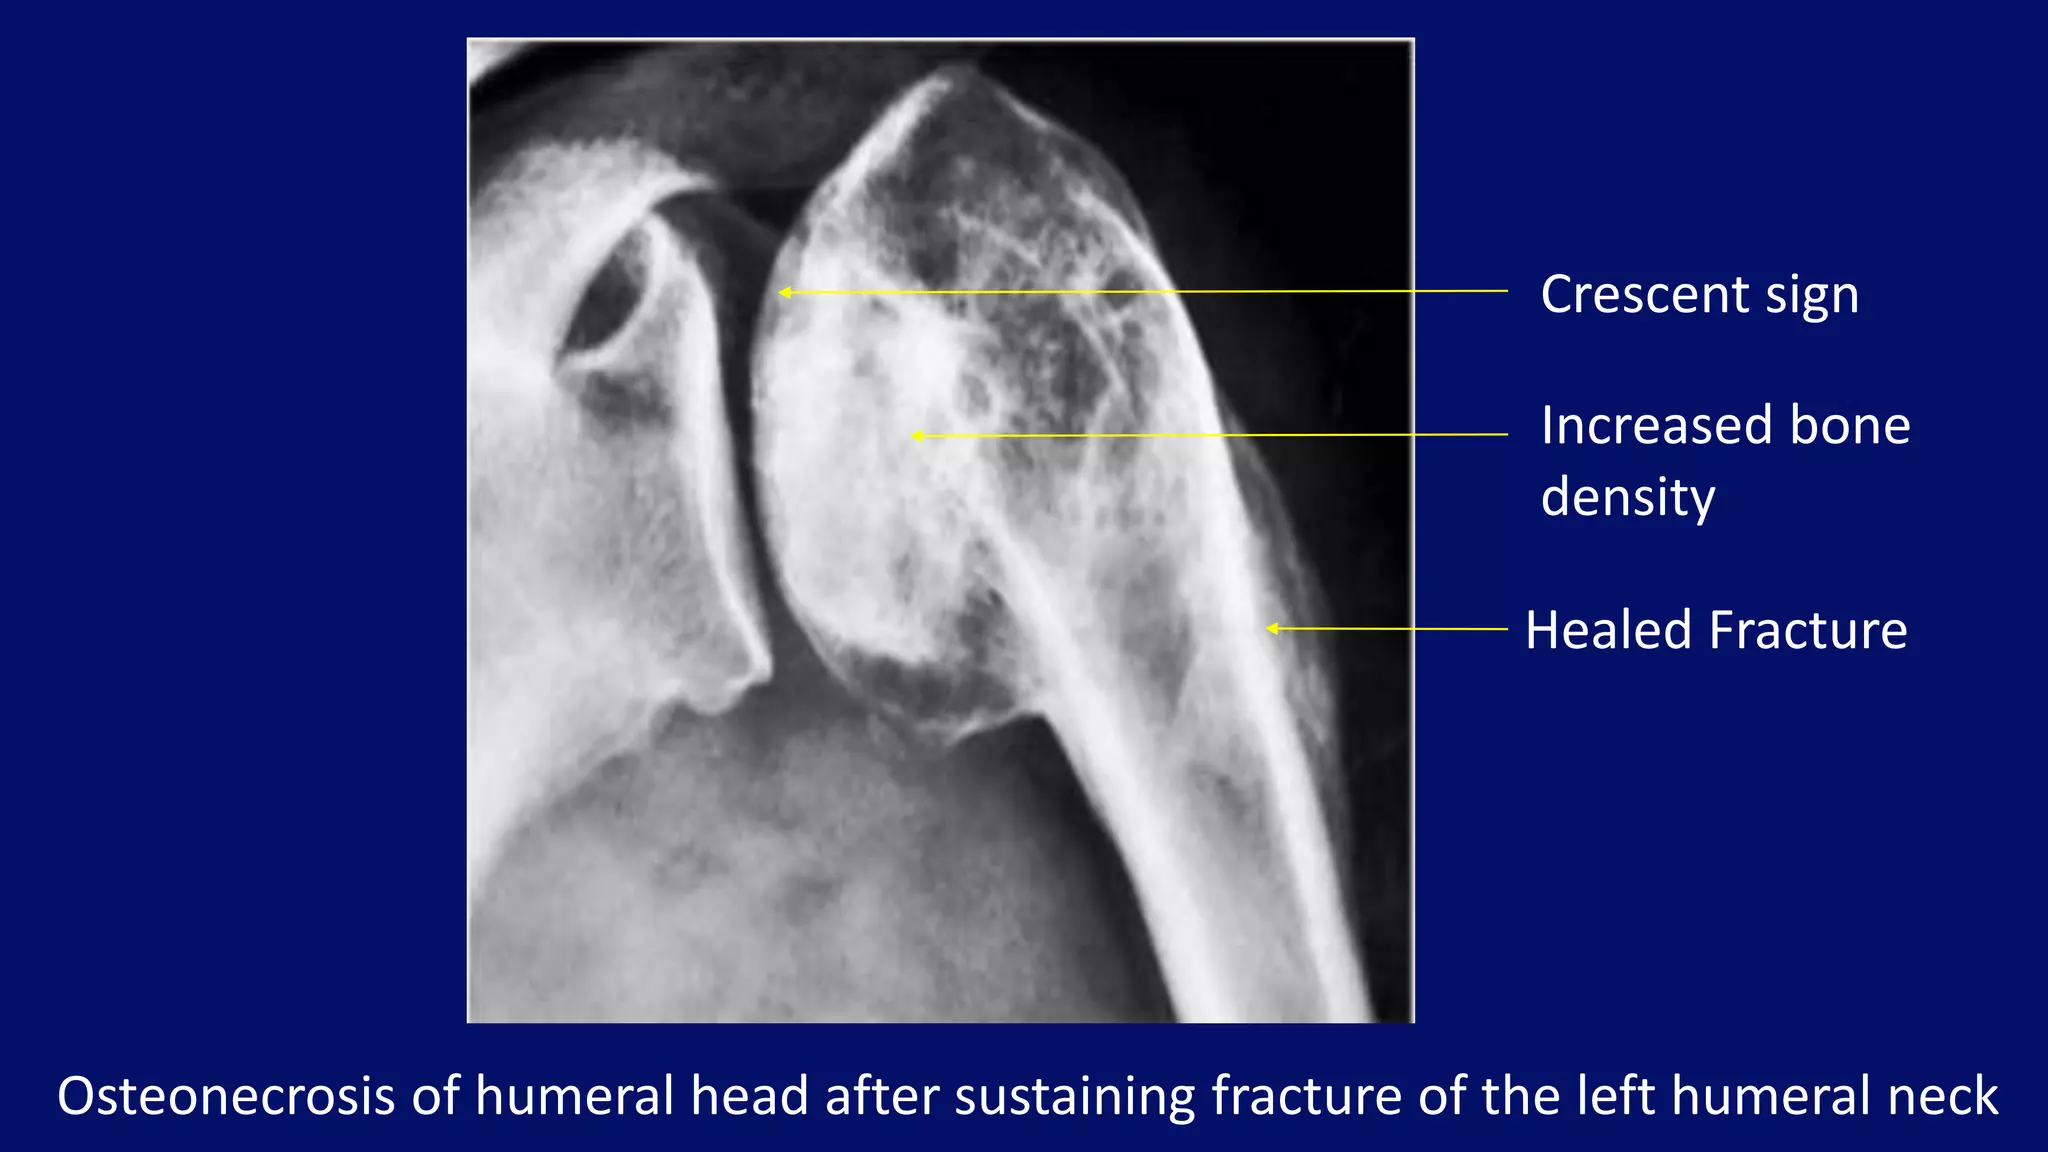

Osteonecrosis of humeral head after sustaining fracture of the left humeral neck

Crescent sign

Increased bone

density

Healed Fracture